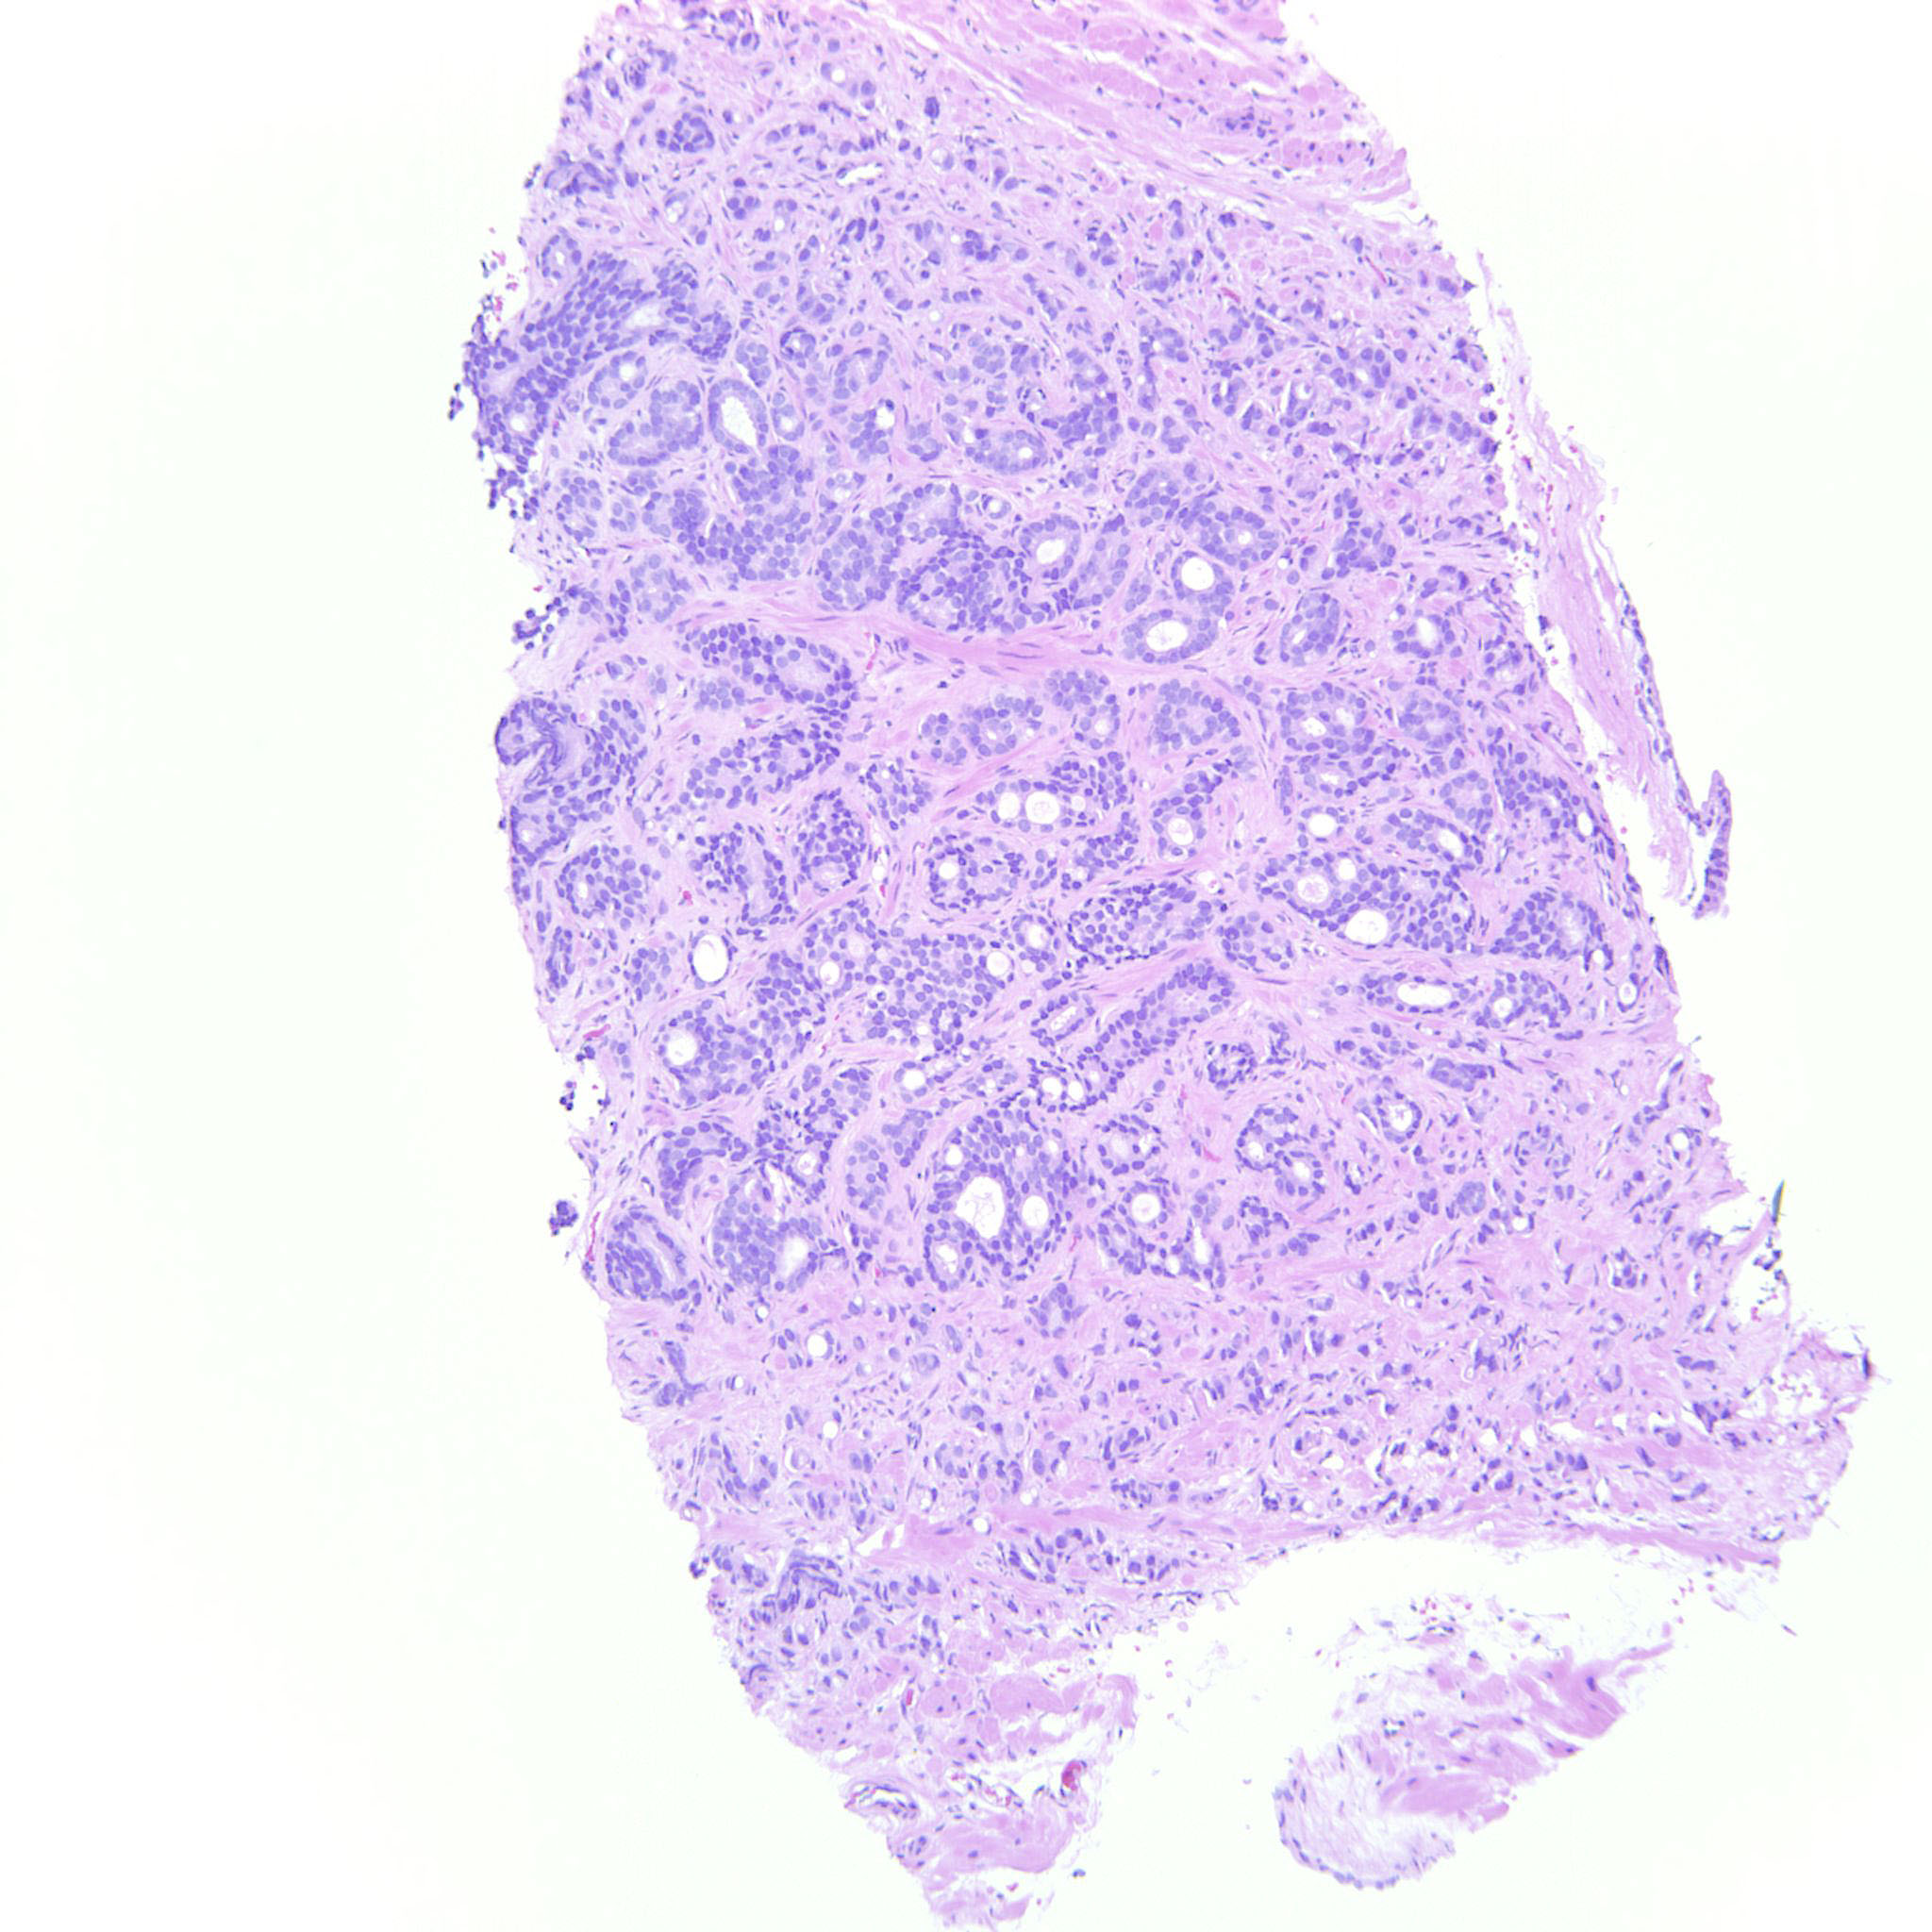

Consensus grade: GS 9-10 (ISUP 5)

Case description (by case creator):

The tumor is dominated by GP4 with mainly cribriform and fused glands but also some poorly formed glands. There is also a component of GP5 with single cells and indian files. These cells occupy an area that can be seen already at 10x. The GP5 component looks immature but is not suspicious for small cell carcinoma.